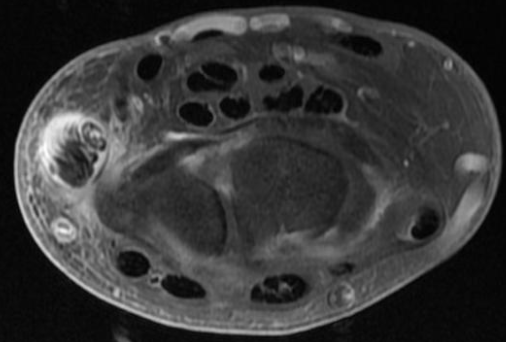

Ténosynovite du Tunnel Carpien